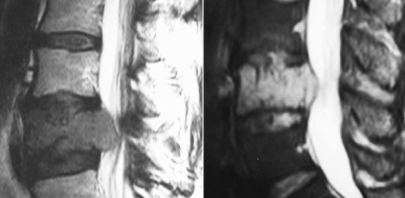

Qual é a anatomia relevante para a lombalgia?

Discos intervertebrais, particularmente o ânulo fibroso e o núcleo pulposo.

Como a idade afeta a degeneração discal?

Com o envelhecimento, os discos perdem hidratação e elasticidade.